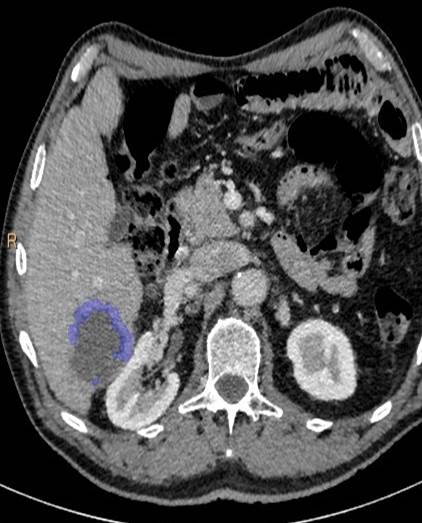

Věnuji se především hodnocení odpovědi na léčbu u hepatocelulárního karcinomu, konkrétně volumetriím po transarteriálních chemoembolizacích. Tato metoda umožňuje zobrazit nádory ve 3D a vypočítat jejich objem, což se jeví přesnější než současné standardní měření v jedné ose. V našem výzkumu se také toto hodnocení ukázalo být jediným faktorem korelace s přežíváním pacientů, což by mohlo ovlivnit jejich léčbu.

Moderní metody terapie jako transarteriální chemoembolizace jsou již i u nás velmi rozšířené. Na našem pracovišti bylo mezi lety 2010 a 2015 provedeno 606 těchto výkonů. Nejedná se však o levnou metodu léčby, proto je důležité stanovit, kteří pacienti z ní mohou opravdu profitovat. Volumetrie se zdá být jedním z ukazatelů účinnosti léčby, tudíž se jedná o velmi slibnou, ač zatím pouze experimentální metodu hodnocení.